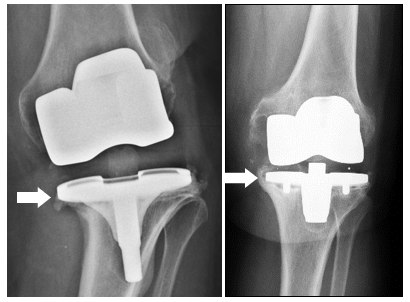

COMMON REASONS for replacing a knee prosthesis include, in addition to infection, instability or persistent pain.

As part of a new knee operation,

special implants necessary to replace defective ligaments (with a so-called

coupled prosthesis ) or to build defects of the bone (by Augment or bone replacement material).